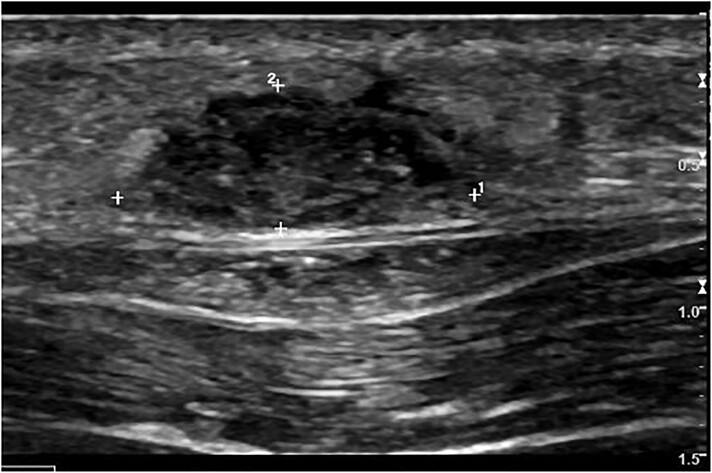

A 2-year-old male with genetic-negative, diazoxide-responsive hyperinsulinism presented with a knot in his left, lateral thigh. His hypoglycemia was managed with diazoxide, chlorothiazide, and monitoring via a Dexcom G6 continuous glucose monitor (CGM). X-ray showed 3 metallic wire foreign bodies, consistent with retained Dexcom sensor wires. He was referred to surgery for foreign body removal. Intraoperative fluoroscopy revealed 4 pieces of wire. Two superficial pieces were removed, but 2 small pieces deep to the fascia remained because of significant risk of injury or bleeding if removal was attempted. We present this case to increase awareness in the literature regarding retention of CGM wires. Raised nodules at sites of CGM insertion without fluctuation or erythema and persistent pain should raise suspicion for retention of sensor wires.

2岁男性,遗传阴性,二氮卓反应性高胰岛素症表现为左外侧大腿结。患者使用二氮氧化物、氯噻嗪治疗低血糖,并通过Dexcom G6连续血糖监测仪(CGM)进行监测。x线显示3个金属丝异物,与保留的Dexcom传感器丝一致。他被转到外科做异物取出手术。术中透视显示4根钢丝。两个表面的碎片被移除,但2个深至筋膜的小碎片仍然存在,因为如果试图移除,有很大的受伤或出血风险。我们提出这个病例是为了提高文献中对CGM金属丝潴留的认识。CGM插入部位隆起结节,无波动或红斑和持续疼痛,应怀疑传感器导线保留。